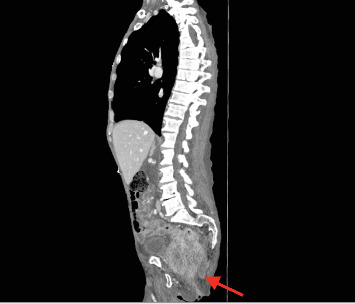

In this paper, we discuss the case of a late presentation, locally advanced rectal cancer that has perforated into the greater sciatic notch, presenting with symptoms of lower limb pain and recurrent falls. In this case, we discuss the complexities of diagnosing and managing atypical presentations of colorectal cancer.